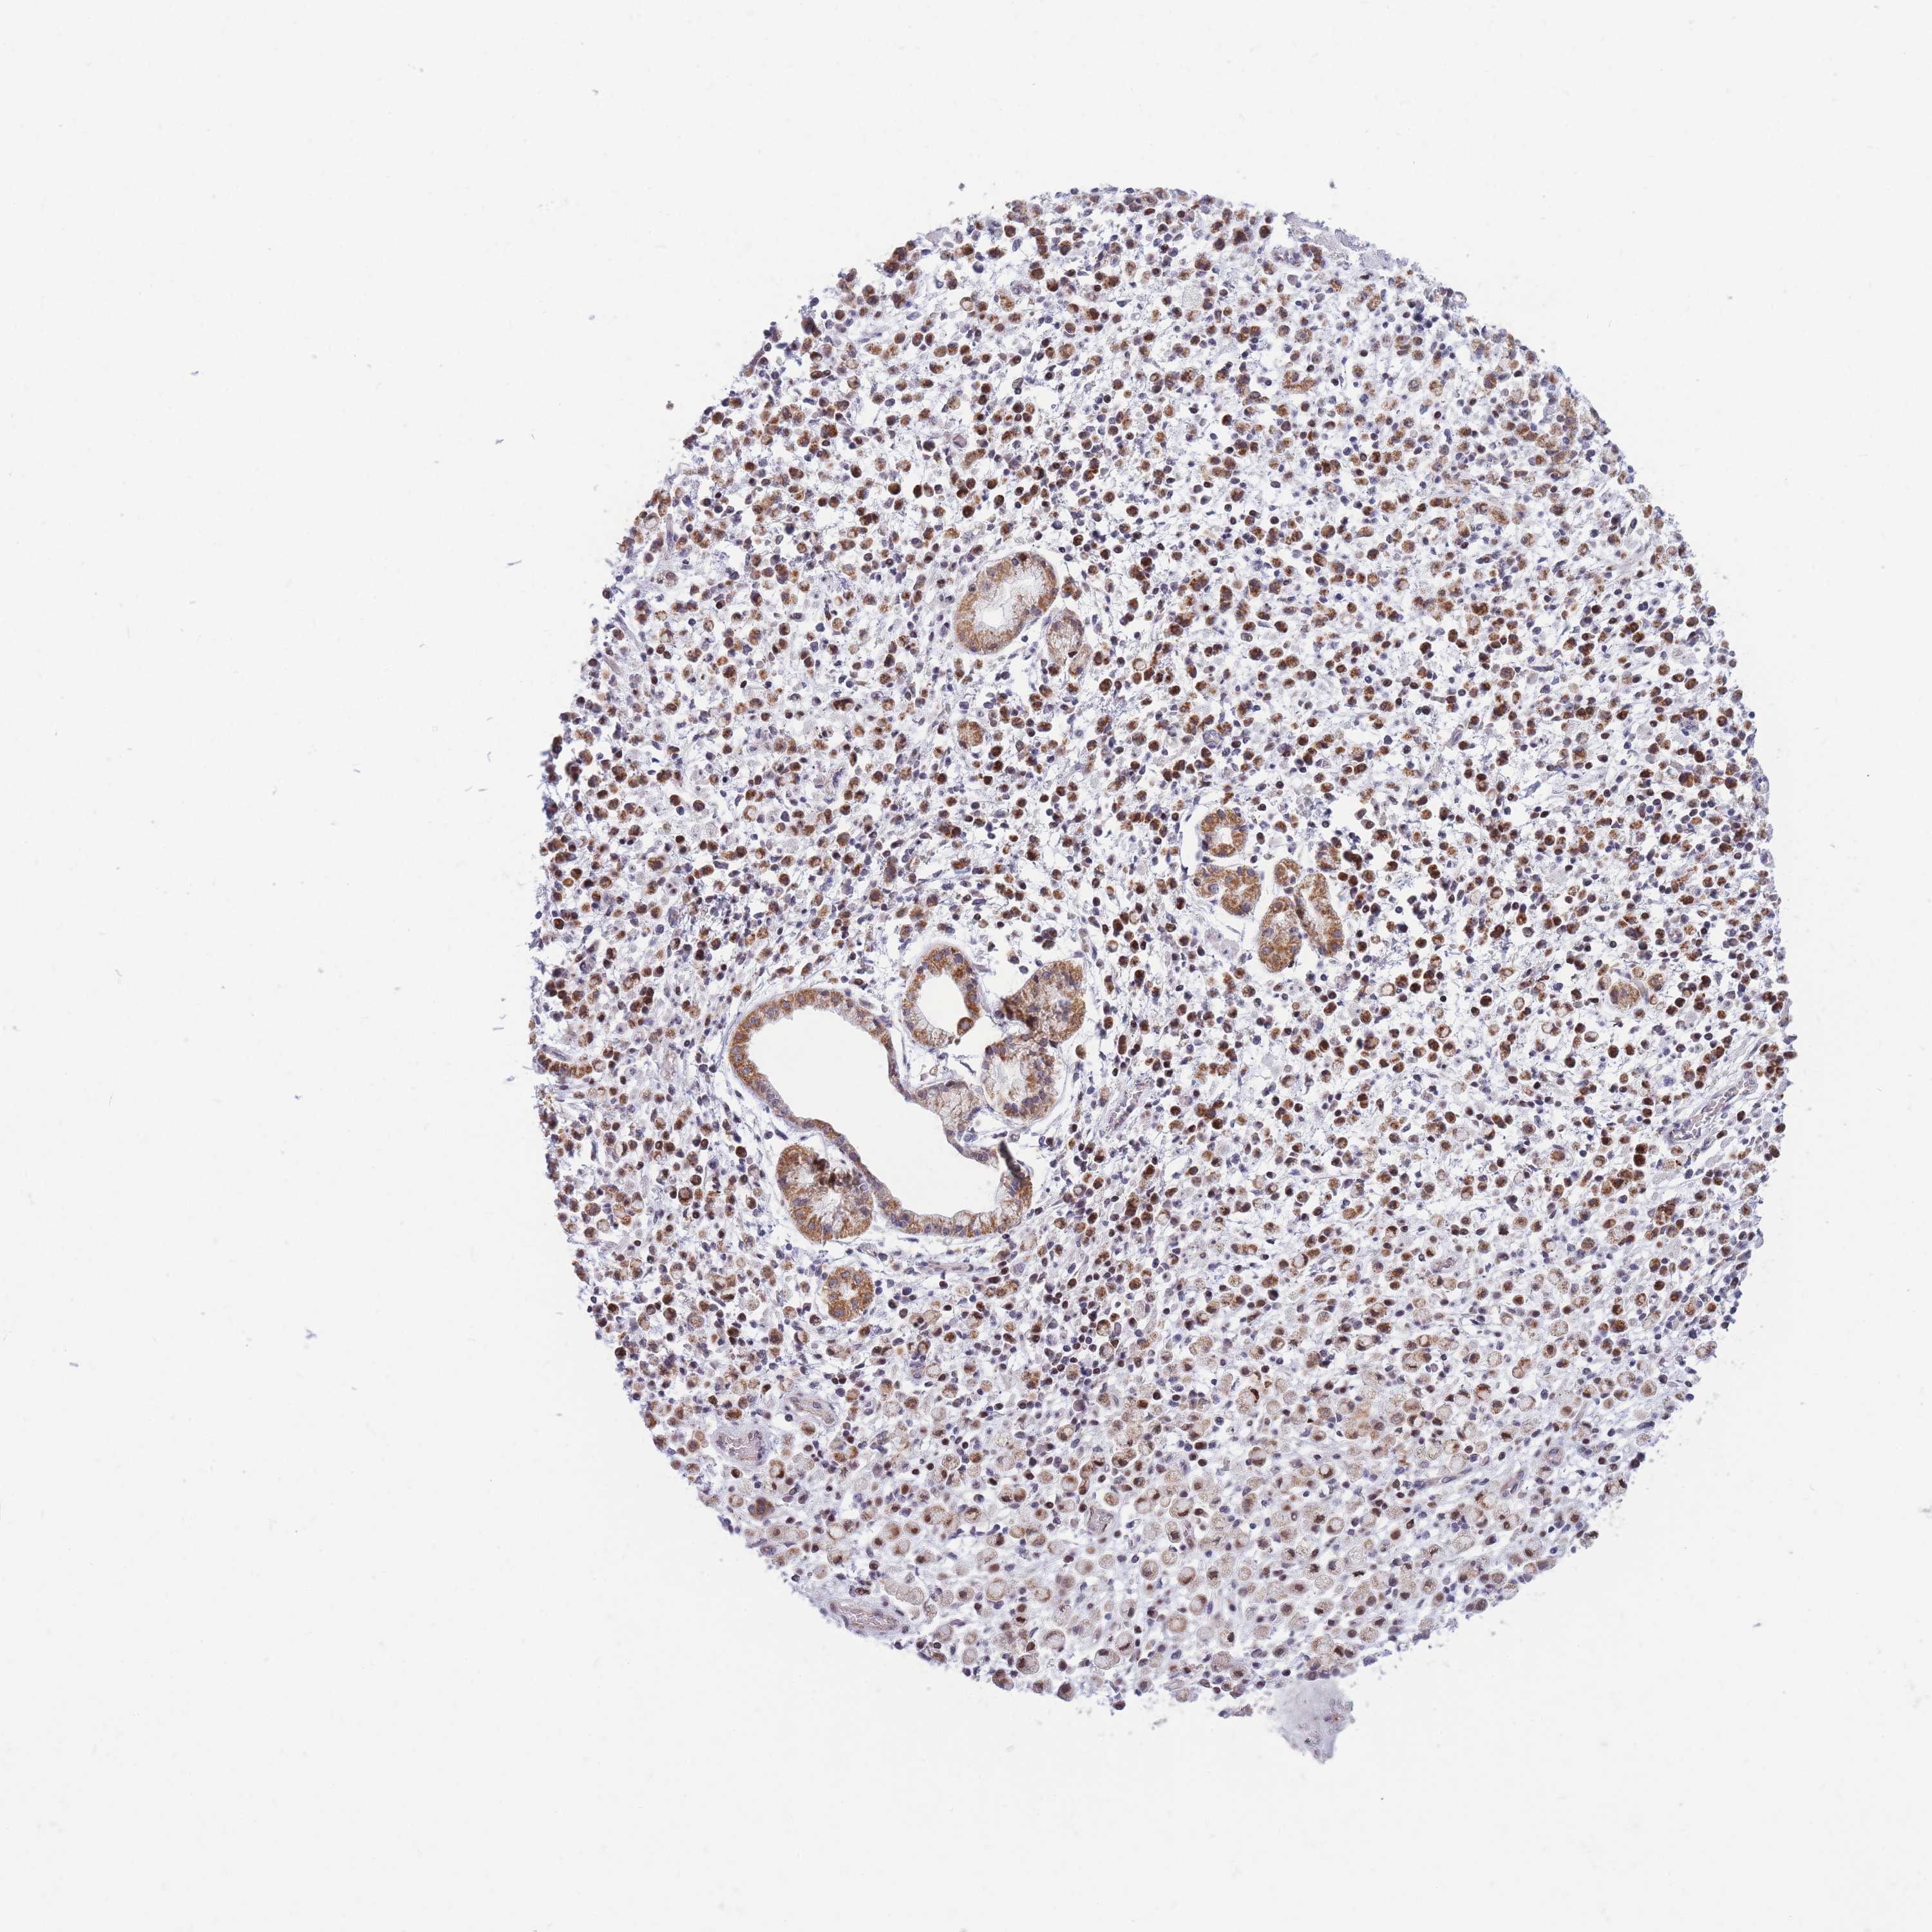

STOMACH CANCER - Protein expressioni

A mouse-over function shows sample information and annotation data. Click on an image to view it in a full screen mode. Samples can be filtered based on level of antibody staining by selecting one or several of the following categories: high, medium, low and not detected. The assay and annotation is described here.

Note that samples used for immunohistochemistry by the Human Protein Atlas do not correspond to samples in the TCGA dataset.

Antibody stainingi

Antibody staining in the annotated cell types in the current human tissue is reported as not detected, low, medium, or high, based on conventional immunohistochemistry profiling in selected tissues. This score is based on the combination of the staining intensity and fraction of stained cells.

Each image is clickable and will lead to virtual microscopy that enables deeper exploration of all samples and also displays staining intensity scores, fraction scores and subcellular localization as well as patient and tissue information for each sample.

Antibody HPA038755

Antibody HPA044125

Antibody HPA048272

Staining

High

Medium

Low

Not detected

Intensity

Strong

Moderate

Weak

Negative

Quantity

>75%

75%-25%

<25%

None

Location

Nuclear

Cytoplasmic/membranous

Cytoplasmic/membranous,nuclear

Adenocarcinoma, NOS